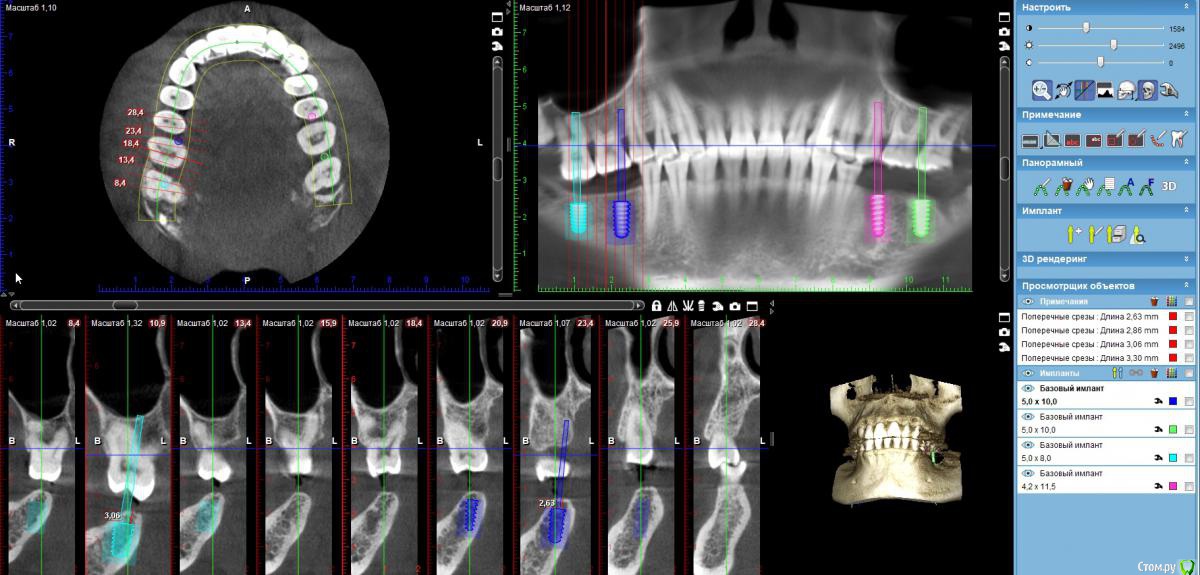

zumanok Опубликовано 13 марта, 2019 Поделиться Опубликовано 13 марта, 2019 Здравствуйте доктора. Пациенту планируется утсановка 4 имплантатов в области 3.5 (имплантат4,2х11,5), 3.7(5х10), 4.6(5х10 или 5х8) и 4,7(5х8 или 4.2х8)Имеется прямой прикус и выдвижение антогонистов со стороны 4.6,4,7, планируется удаление кости мм на 2-3 Встал вопрос будут ли держать оптимальную нагрузку имплантат размерами 5х8 и 4.2х8 или лучше поставить побольше но под небольшим углом.На снимках 4.6(5х10) и 4,7(5х8).Да и вообще долго задаюсь вопросом какой наименьший размер и диаметр имплантата является оптимальным для каждого зуба?Благодарю за совет. Ссылка на комментарий

Дмитрий М Опубликовано 17 апреля, 2019 Поделиться Опубликовано 17 апреля, 2019 (изменено) Здравствуйте доктора. Пациенту планируется утсановка 4 имплантатов в области 3.5 (имплантат4,2х11,5), 3.7(5х10), 4.6(5х10 или 5х8) и 4,7(5х8 или 4.2х8)Имеется прямой прикус и выдвижение антогонистов со стороны 4.6,4,7, планируется удаление кости мм на 2-3 Встал вопрос будут ли держать оптимальную нагрузку имплантат размерами 5х8 и 4.2х8 или лучше поставить побольше но под небольшим углом.На снимках 4.6(5х10) и 4,7(5х8).Да и вообще долго задаюсь вопросом какой наименьший размер и диаметр имплантата является оптимальным для каждого зуба?Благодарю за совет.у пациента повышенная стираемость судя по снимку 2-3 мм редуцировать кость? не многовато лисовсем не останется прикрепленки, которой там судя по картинке и без того мало. +1 к варианту stommm. коррекция 16,17.; кость не трогать Изменено 17 апреля, 2019 пользователем Дмитрий М Ссылка на комментарий

zumanok Опубликовано 21 мая, 2019 Автор Поделиться Опубликовано 21 мая, 2019 у пациента повышенная стираемость судя по снимку 2-3 мм редуцировать кость? не многовато лисовсем не останется прикрепленки, которой там судя по картинке и без того мало. +1 к варианту stommm. коррекция 16,17.; кость не трогатьОперацию сделал, поставил, 4.6-4.2х10 и 4.7- 5х8. Гребень все же немного подсрезал 1-2 мм. 1 Ссылка на комментарий